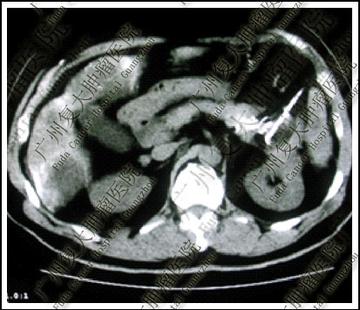

王家三口平時經常出現吃飯前後肚子痛的狀況,一開始都當作腸胃小毛病沒放在心上。直到有天兒子體重狂掉,從原本60公斤左右一路降到45公斤,這才緊急衝醫院檢查。結果醫師發現他的胰臟長出腫塊,血液數值也不正常,確診為胰臟癌。醫師表示,持續的腹部疼痛加上體重急速下降,都跟體內腫瘤逐漸變大有關。

王男聽到兒子罹癌後嚇壞,想起自己和老婆也有類似症狀,趕緊帶全家一起做檢查,沒想到結果出爐,夫妻倆也都確診,一家3口全罹患胰臟癌!畢竟癌症不會傳染,醫療團隊排除遺傳基因因素後,把調查方向轉向他們的日常飲食。